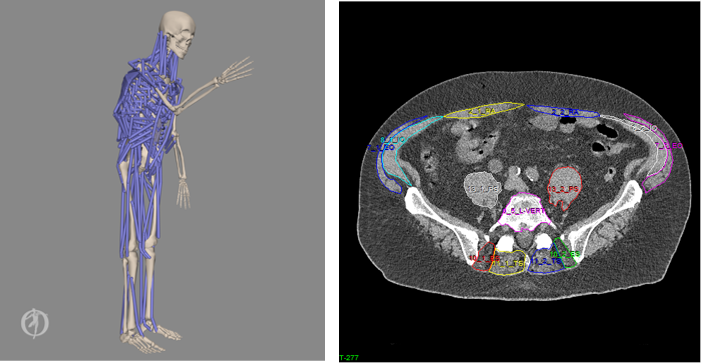

Patients treated with radiation therapy for metastatic disease of the spine suffer high risk for pathologic spinal fractures (PVF) – up to 39% sustaining a fracture within 6 months. Clinical guidelines for estimating fracture risk remain subjective, and improved, individualized prediction of PVF risk would facilitate selection of whether, how, and when to intervene. This study will examine whether estimates of spinal loading to vertebral strength will improve predictions of the risk of PVF compared to current clinical protocols in a patient cohort. Our lab is obtaining spine curvature and muscular measurements from CT data, then generating patient-specific musculoskeletal models to assess biomechanical loads experienced when doing everyday tasks, such as opening a window or getting up from bed. Such a quantitative assessment of biomechanical risk could fill a significant gap in the ability to evaluate and treat these patients. This study is a collaboration with Ron Alkalay, Ph.D., in the Department of Orthopaedic Surgery.